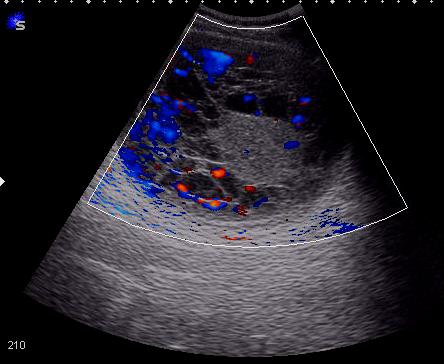

KapustinSV писал(а):Доплер?

-доплер.jpg

Так есть ли воспроизводимый кровоток или нет? - На представленной сонограмме в режиме ЦДК очень высокий уровень цветовых шумов из-за большого усиления - возможны ошибки в интерпретации.

Если кровоток есть, то правомерно заключение "RCC".

Нет - остается "объемное образование почки", рекомендуется КТ.

При клинической необходимости несложно выполнить тонкоигольную диагностическую биопсию образования.